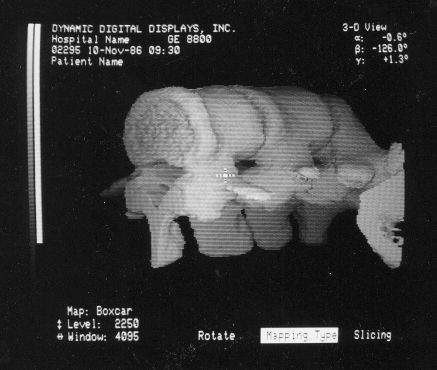

These photos of the Voxelscope II screen are typical of the types of rendering provided by the system.

Voxelscope II Screen Shots. Combination of 3-D Shaded Surface, Multiplanar Reformatting, and Segmentation